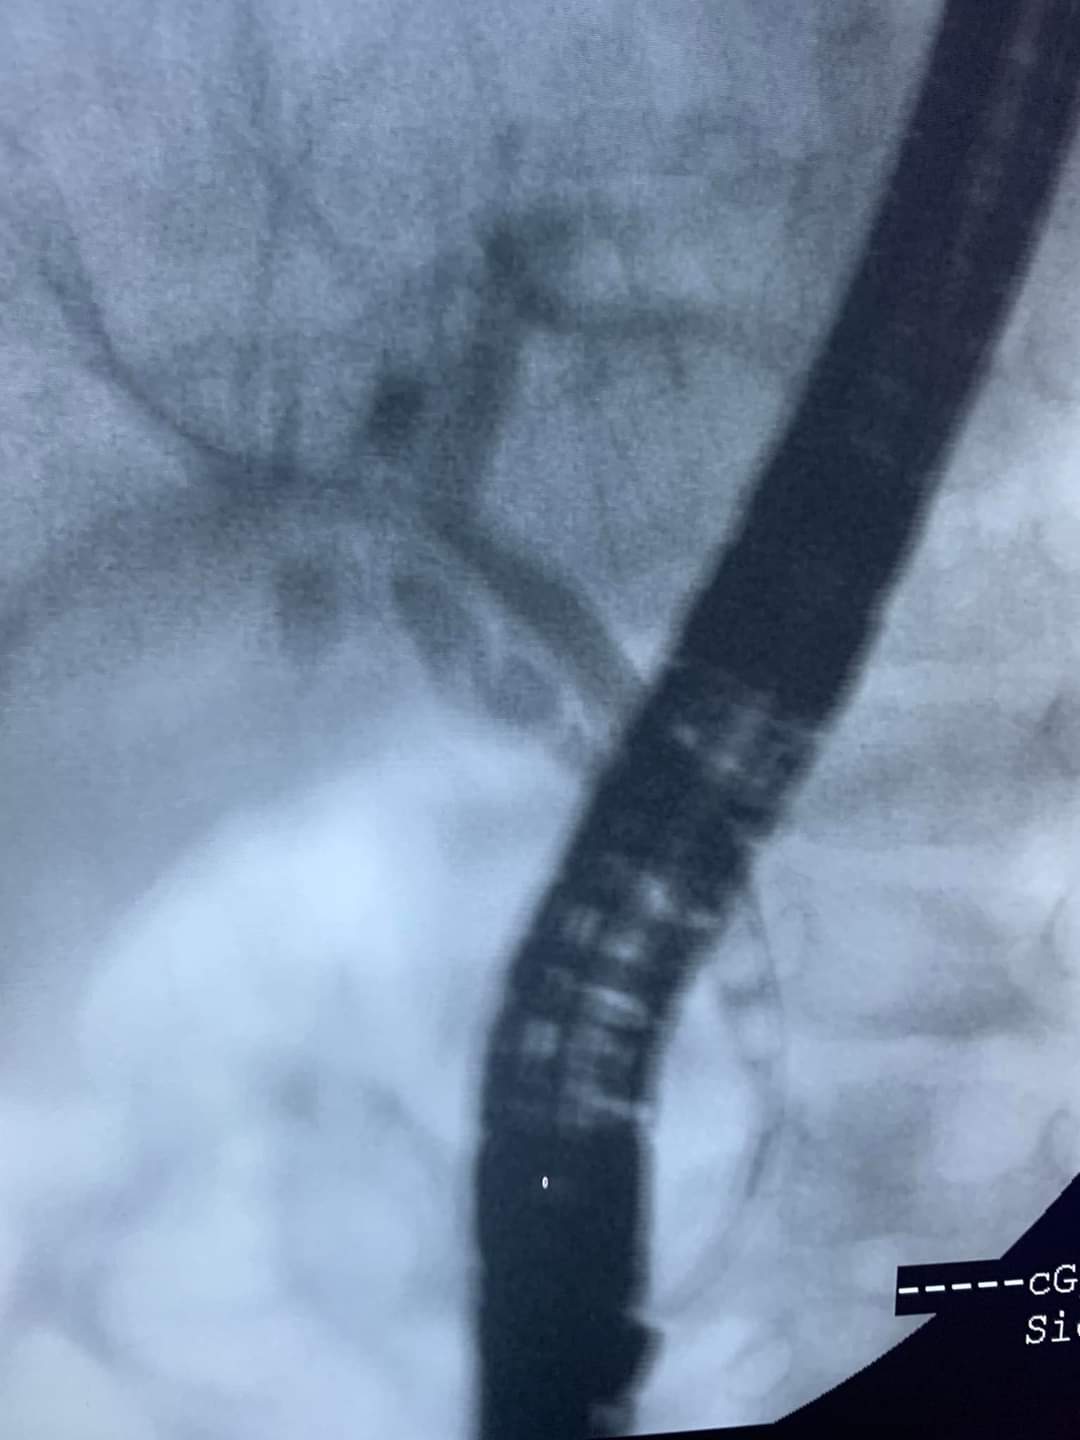

أجرى الدكتور عصام الشيمي الأستاذ بمعهد الكبد القومي بالمنوفية، عملية منظار لطفلة عمرها 8 أشهر، وذلك عقب حضورها لمستشفى معهد الكبد في حالة سيئة، وتعاني ارتفاع نسبة الصفراء وانسداد في القنوات المرارية بسبب وجود حصوتين، في واحدة من الحالات النادرة.

وأضاف الشيمي، لـ القاهرة 24، أن حالة الطفلة كانت صعبة وتم اتخاذ القرار وفق الرأي الطبي أنه لا يوجد حل إلا المنظار، واستغرقت العملية 20 دقيقة، كانت كفيلة بتسليك القنوات المرارية واتخاذ الإجراءات الطبية اللازمة تجاه الطفلة، وخرجت من المستشفى بعد تحسن حالتها الصحية.